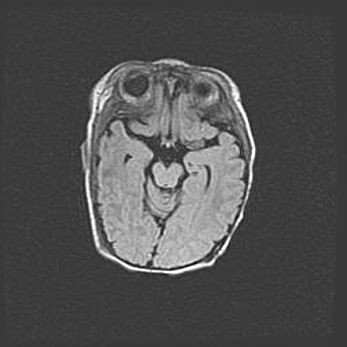

Наружная гидроцефалия с возможной атрофией височных областей.

Возраст: 28 дней

Вес: 3670 г

Пол: мужской

Окружность головы: 38 см

Срок гестации: 40 недель

Гидроцефалия головного мозга у новорожденных – это заболевание, которое характеризуется скоплением избыточного количества спинномозговой жидкости в желудочковой системе головного мозга в результате затруднения её перемещения от места выработки к месту поглощения в кровеносную систему или вследствие нарушения абсорбции. При открытой наружной форме гидроцефалии у новорожденных расширяются и переполняются субарахноидные пространства.

При нормотензивных  формах,  которые,  как  правило,  являются  следствием  перенесенных ишемических  повреждений  паренхимы  мозга,  возможно  сочетание микроцефалии  с нормотензивной гидроцефалией. В основе данных изменений лежит атрофия больших полушарий с преимущественной  локализацией  в  лобно-височных  областях.